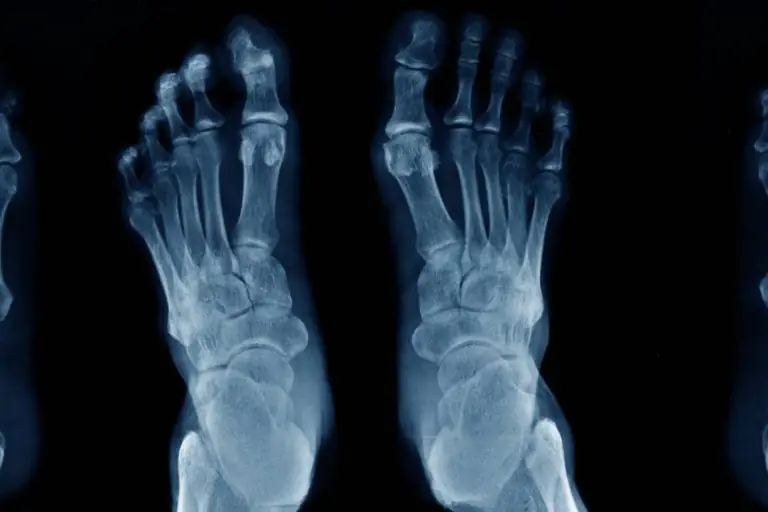

Radiografia del Piede destro e/o sinistro (per alluce valgo o piede piatto)

La radiografia del piede è un esame radiologico eseguito mediante l’utilizzo di Raggi X, che riescono ad attraversare il corpo e restituire un’immagine digitale (o su pellicola) che è in grado di evidenziare in modo differente le ossa dello scheletro rispetto ai tessuti molli circostanti.

L’esame viene eseguito attraverso tecnologia digitale. Il risultato è rappresentato da immagini radiografiche di qualità diagnostica nettamente superiore rispetto a quelle prodotte con la vecchia tecnologia analogica ed una più snella ed efficiente metodologia di archiviazione. Si possono eseguire:

- Proiezioni standard: dorso plantare, obliqua, laterale

- Proiezioni standard sotto carico

- Proiezioni aggiuntive: indicate dal Medico in base alla necessità del paziente